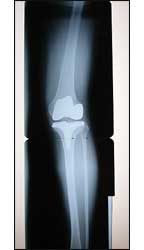

![]() |

| Using CPM following fracture repairs can promote better healing. |